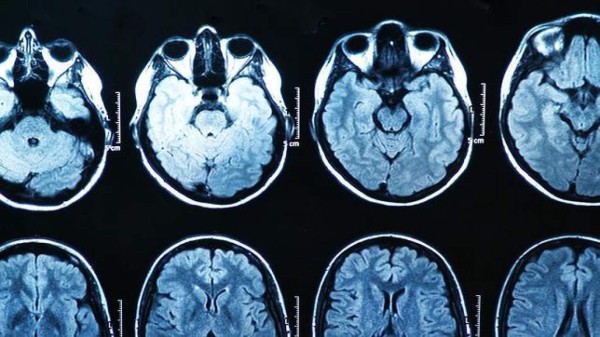

Traumas como los del 11-S hacen que el cerebro, concretamente una región conocida como amígdala, se vuelva más sensible al miedo, incluso para personas sanas que vivían a centenares de kilómetros de la tragedia, según un estudio de la Universidad de Cornell que publicaba la revista Emotion. En una serie de experimentos usando resonancia magnética funcional, los investigadores comprobaron que la reacción cerebral era más intensa de lo habitual en centenares de sujetos cuando se les mostraban caras de personas asustadas. Ninguno de los sujetos sufría problemas psiquiátricos.

Cerebro encogido

Muchos estudios dirigen que la causa es el trauma por los atentados.

La cantidad de materia gris de los centros cerebrales que regulan las emociones se redujo considerablemente en los adultos que se encontraban cerca del World Trade Center durante el ataque terrorista, según un estudio publicado en la revista especializada Neuroimagen en abril de 2008. El descenso en el volumen de materia gris podría ser una respuesta normal del cerebro ante un trauma, según concluía Barbara Ganzel, coautora del trabajo.